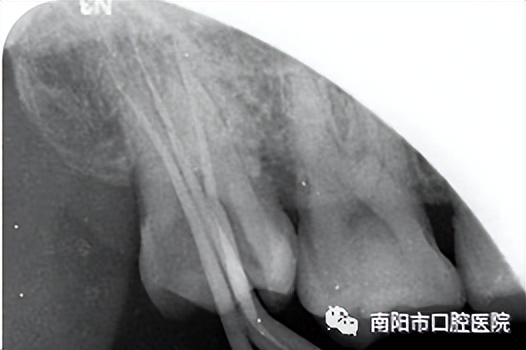

对于遇冷热刺激有敏感疼痛感或有咬合不适感的中度隐裂牙,急性牙髓感染时会产生剧痛。这种隐裂牙医生会根据需要做完善的根管治疗,同时调整牙尖斜度,治疗后及时进行牙冠修复。

根管治疗后全瓷冠修复